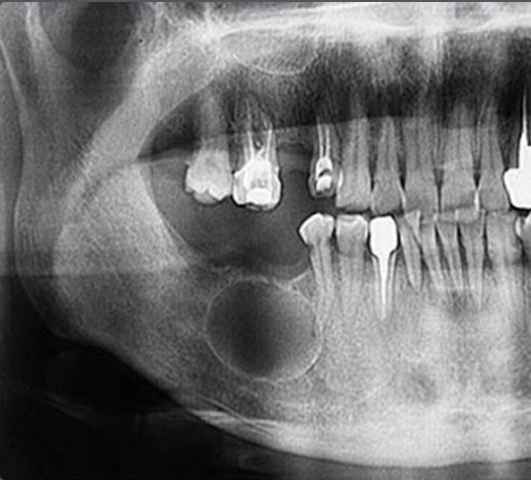

Корневые кисты – это рентгенопрозрачные капсулы с четкими границами, размеры которых варьируются от 2-3 мм до 2-3 см. В большинстве случаев они развиваются бессимптомно, если не осложнены вторичным воспалением. Даже крупные образования не вызывают смещения зубов или расширения костной ткани.

Остаточная киста легко обнаруживается на рентгеновском снимке. Размеры варьируются от нескольких миллиметров до нескольких сантиметров.

Киста в десне развивается из фолликулярного мешочка, окружающего непрорезавшийся зуб. На рентгеновском снимке выглядит как капсула, чаще всего расположенная вокруг коронки такого зуба. Может вызывать значительные повреждения зуба, характеризуется быстрым ростом, способным смещать соседние зубы и приводить к расширению кортикальной пластинки.

Формируется из зубного зачатка из-за дегенерации звездчатого ретикулума в процессе развития зуба до начала кальцификации его тканей. Эти кисты могут возникать из любого зубного зачатка, но чаще всего локализуются в области премоляров и третьих моляров нижней челюсти.

Их этиология также до конца не установлена. Такие кисты могут быть обнаружены в любой части опорной поверхности челюстей, но чаще всего в нижней. Морфологически они имеют разнообразные формы. На рентгеновских снимках они четко видны и могут содержать различные помутнения в зависимости от степени кальцификации новообразования. После постановки диагноза лечение включает хирургическое выскабливание или резекцию.